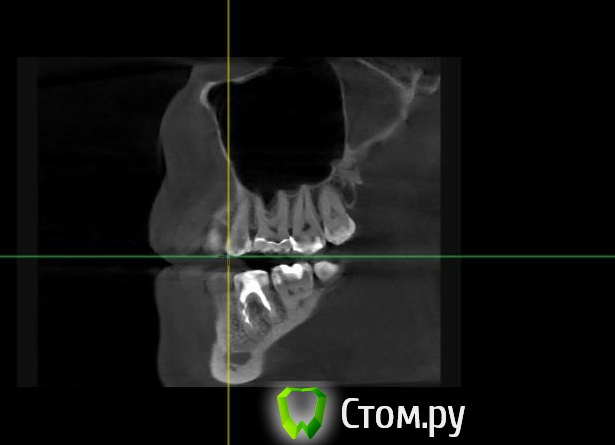

Майло Опубликовано 18 марта, 2014 Автор Поделиться Опубликовано 18 марта, 2014 (изменено) Здравствуйте, наконец сделала кт. Сегодня появилась небольшая боль над правой бровью (после лазера прошла, к вечеру появилась опять). Насморк и заложенность присутствуют. Еще сегодня опять поговорила со своим хирургом имплантологом. По симптомам сказал, что похоже присоединилась какая-то лор болячка и наверное надо сходить к лору. По кт сказал, что все нормально. Немного сужена пазуха справа, но учитывая, что я аллергичная, это нормально. Про капли типа Полидекса, сказал спросить у лора. Завтра я делаю последний лазер, по прежнему промываю нос Отривином Бэби (мне так удобней), пью кларитин, "выбиваю" нос по необходимости, но стараюсь пореже (2-3 раза в день). Еще он отдал кт через 2 недели после имплантации, на всякий случай прикреплю и этот снимок. Самый первый снимок кт был сделан через 2 недели после имплантации. Второй и третий сегодня. Подскажите, я так понимаю данное кт не показывает есть ли у меня гайморит? (к лору смогла записаться аж на 26-е) И все равно хотелось бы узнать ваше мнение по поводу состояния имплантов, есть ли там воспаление или "нагноение"? Изменено 18 марта, 2014 пользователем Майло Ссылка на комментарий

Майло Опубликовано 18 марта, 2014 Автор Поделиться Опубликовано 18 марта, 2014 (изменено) Решила еще добавить пару кадров своих пазух, вначале показалось что справа что-то есть (рис1), потом поняла это костный материал и импланты (рис2). Надеюсь так должно быть. И еще вопрос, может и "тупой", такое яркое свечение имплантов, особенно заметно на фото в профиль, это нормально? Изменено 18 марта, 2014 пользователем Майло Ссылка на комментарий

Bier Опубликовано 18 марта, 2014 Поделиться Опубликовано 18 марта, 2014 выглядит все неплохо, и пазуха чистая. Гайморита у вас нет. Сходите к ЛОРУ 2 Ссылка на комментарий

Майло Опубликовано 19 марта, 2014 Автор Поделиться Опубликовано 19 марта, 2014 (изменено) выглядит все неплохо, и пазуха чистая. Гайморита у вас нет. Сходите к ЛОРУСпасибо. А такие затемнения вокруг имплатов, это нормально? Изменено 19 марта, 2014 пользователем Майло Ссылка на комментарий

red_butler Опубликовано 19 марта, 2014 Поделиться Опубликовано 19 марта, 2014 Да, это артефакты вызванные металлом Ссылка на комментарий